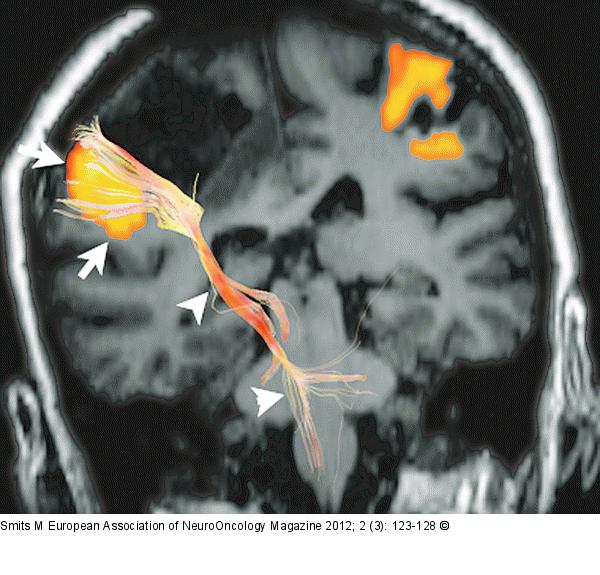

Figure/Graphic 4: Brain tumour Combined fMRI and DTI tractography in a coronal view of a patient with a tumour near the primary motor cortex. Displacement of both the primary motor cortex (arrows) and the corticospinal tract (arrowheads) is seen. |

Combined fMRI and DTI tractography in a coronal view of a patient with a tumour near the primary motor cortex. Displacement of both the primary motor cortex (arrows) and the corticospinal tract (arrowheads) is seen. |